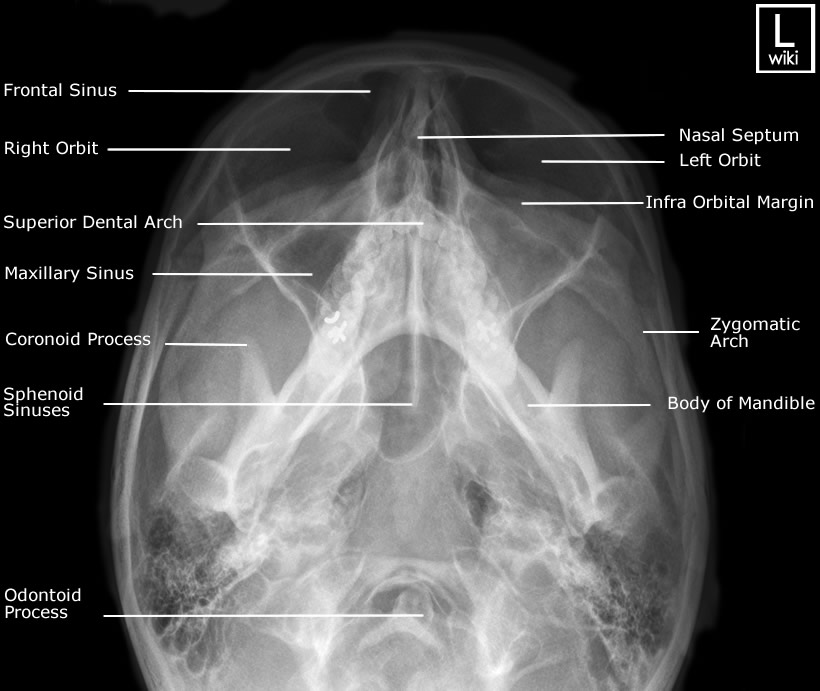

Waters View X Ray Normal . The most useful view for evaluation of midface fractures is the waters's view. Observation of the face (particularly the orbits, maxillary sinuses, and nasal cavities) from the front. The towne's view permits good delineation of the condylar necks. Fractures (particularly tripod and le forte fractures) and neoplastic/inflammatory are shown. No displaced facial or skull fracture noted. Normal transparency of the maxillary and frontal sinuses, no sign of opacification (which would.